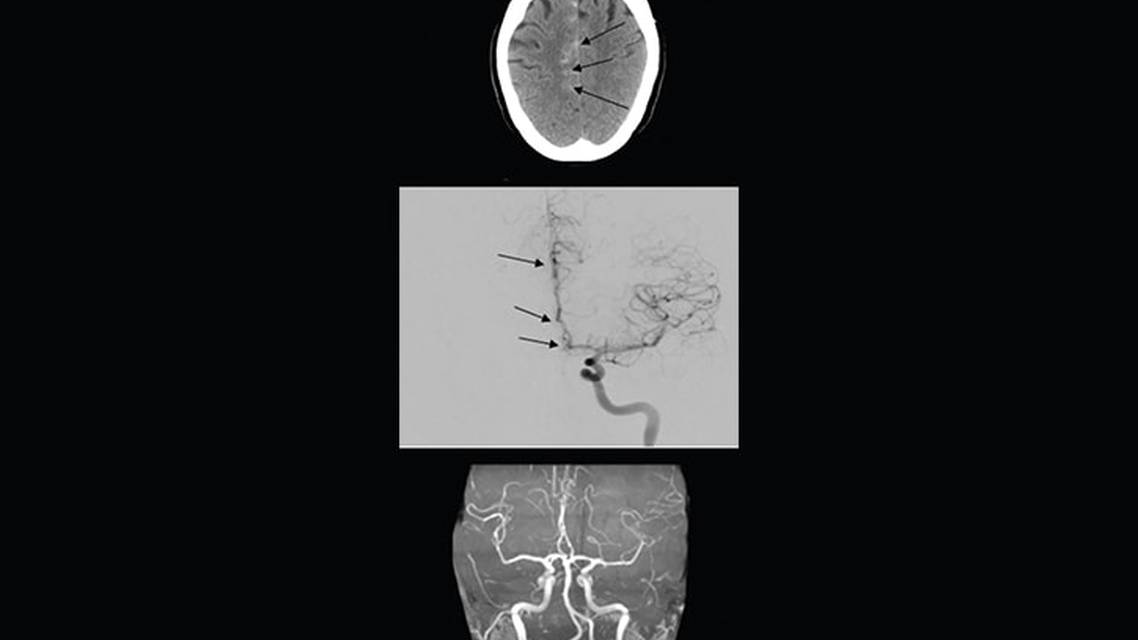

JP, age early 50s, presented to the clinic with the chief complaint of thunderclap headache 1 week after uptitration of phenelzine. JP had a medical history of panic attacks when taking a monoamine oxidase inhibitor. CT head scan showed evidence of SAH (Figure part A). Angiography showed areas of vasospasm and narrowing of the anterior cerebral artery (Figure part B). A “string of beads” appearance of the anterior cerebral artery was identified. Clinical presentation (thunderclap headache) and radiographic findings (SAH and vasoconstriction) shortly after dose increase of a monoamine oxidase inhibitor was consistent with the diagnosis of RCVS. JP scored 10/10 on the RCVS2 scale, further supporting the diagnosis.11

Phenelzine was discontinued and intravenous nicardipine was initiated, which was later converted to oral extended-release verapamil 180 mg daily. Follow-up magnetic resonance angiography 2 months after diagnosis showed normalization of blood vessels (Figure part C).